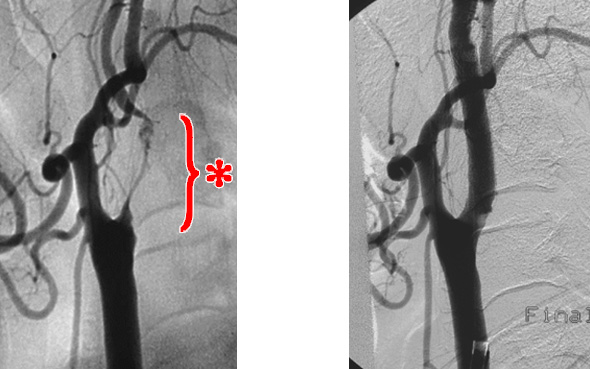

【頸動脈ステント留置術】

頸動脈に狭窄病変があり、薬による内科的治療だけでは今後脳梗塞を発症・再発してしまう可能性が高い場合にお勧めする手術です。

既にこの狭窄病変(中等度~高度な狭窄)が原因で脳梗塞が生じた患者さんや、これまで脳梗塞を起こしていない(無症候性)が高度な狭窄病変を有する患者さんにこの手術を検討します。

足の付け根から直径3mm程度のカテーテルを血管の中へ挿入し、頸部の狭窄病変近くまで誘導した後に、狭窄部位を風船で拡げたり、ステントと呼ばれる網目状の金属の筒を留置することで、血管の内側に付着したプラーク(脂)を血管の外側へ圧着させます。そうすることで減少していた脳への血液の量を改善し、また脆いプラークが飛散して頭蓋内血管を塞栓することで生じる脳梗塞を予防できます。

右:ステントによって狭窄が改善しています。

また狭窄病変を拡げる際に脆いプラークが飛散しないように、病変手前でカテーテル先端に付いた風船を膨らませることで一時的に血流を遮断したり、病変より遠い位置で飛散したプラークを回収する網を留置するなどの工夫をしております。

基本的には局所麻酔で行い、傷の大きさはカテーテルが入っていた片方の足付け根に数ミリ程度のため、身体への侵襲が極めて少ない治療です。

それでも少量のプラークが飛散して術後に脳梗塞を生じたり、術後数日の間で柔らかいプラークがステントの内側にせり出して追加治療を要することがあります。また極めて稀ですが術後には脳への血流が急激に増加することで、脳の血管が対応できずに過灌流という状態(血液が過剰に流れている状態)となり、脳が浮腫んだりまた最悪の場合は脳出血を起こすこともあるため、当院では術後もしばらくは徹底した脳血流の管理を行っております。